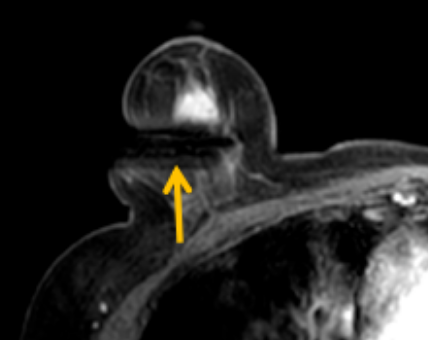

陳寶瑩評估圖像后發(fā)現(xiàn)病變?yōu)閮H僅在磁共振增強時顯示,為非腫塊樣病變,比較散,必須取得足夠多的組織才能確保病理檢查的準確性,常用的核芯針活檢獲取的組織較少,因此最終確定了磁共振引導下行真空輔助抽吸旋切活檢。取得患者及家屬認可后,陳寶瑩帶領(lǐng)團隊開始進行術(shù)前準備。

針對患者乳房小固定難度大這一問題,陳寶瑩通過巧妙體位和固定器的調(diào)整,順利固定好乳房。經(jīng)過磁共振多模態(tài)掃描,陳寶瑩找出病變活性成分相對集中區(qū)域,精準確定穿刺路徑,置入引導針、旋切針,到位后多角度旋切取出足量組織,拔除旋切針后即時行磁共振掃描,精準取得組織且術(shù)區(qū)出血很少,遂加壓包扎,整個過程非常順利,旋切活檢后患者回家休息。兩天后隨訪,李女士沒有任何不適,五天后皮膚上幾毫米的小切口已經(jīng)愈合。最終病理結(jié)果證實為乳腺導管原位癌,為早期乳腺癌,為患者后續(xù)針對性治療奠定了基礎。